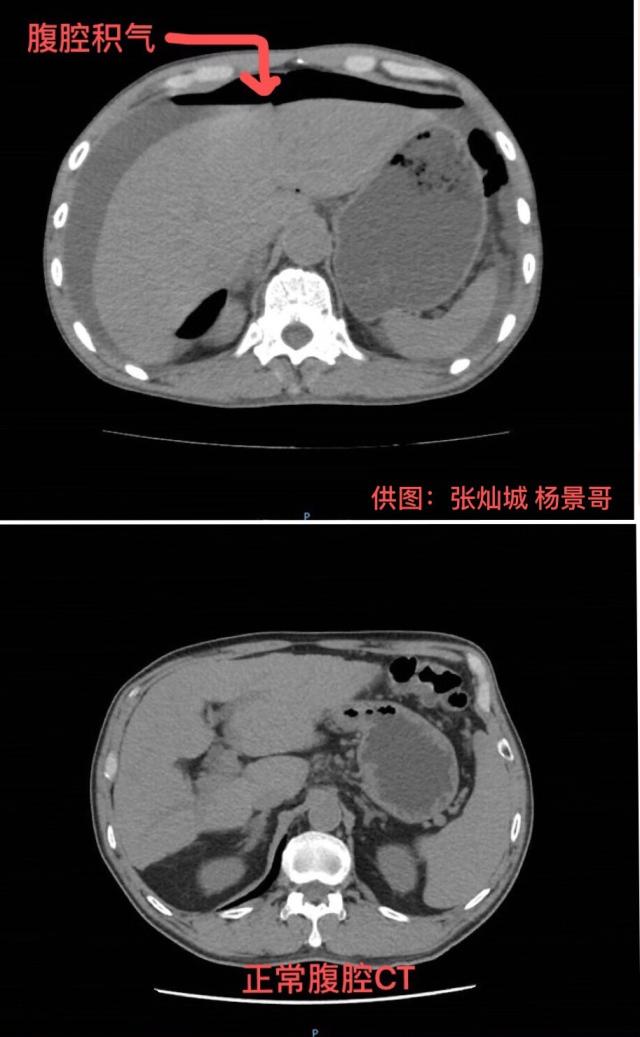

当时,陈伯腹中因大量积水而肿胀发硬,还出现了无尿症状,腹部皮肤因供血不够已出现“花斑”。结合进一步检查结果,诊断为胃穿孔弥漫性腹膜炎感染性休克。“如果不做手术,熬不过当晚。但进行手术,也有极大的风险。”汤汉林说。

暨南大学附属第一医院麻醉科主任医师李雅兰和团队维持着陈伯的生命体征,胃肠外科手术团队迅速进行手术。胃肠外科副主任医师杨景哥介绍,术中从陈伯腹部抽出了2500毫升黄绿色脓液,相当于两支可乐“大炮”,感染十分严重。胃壁上有直径1.5厘米的穿孔,胃液伴随食物残渣就是通过这个洞涌入腹腔。